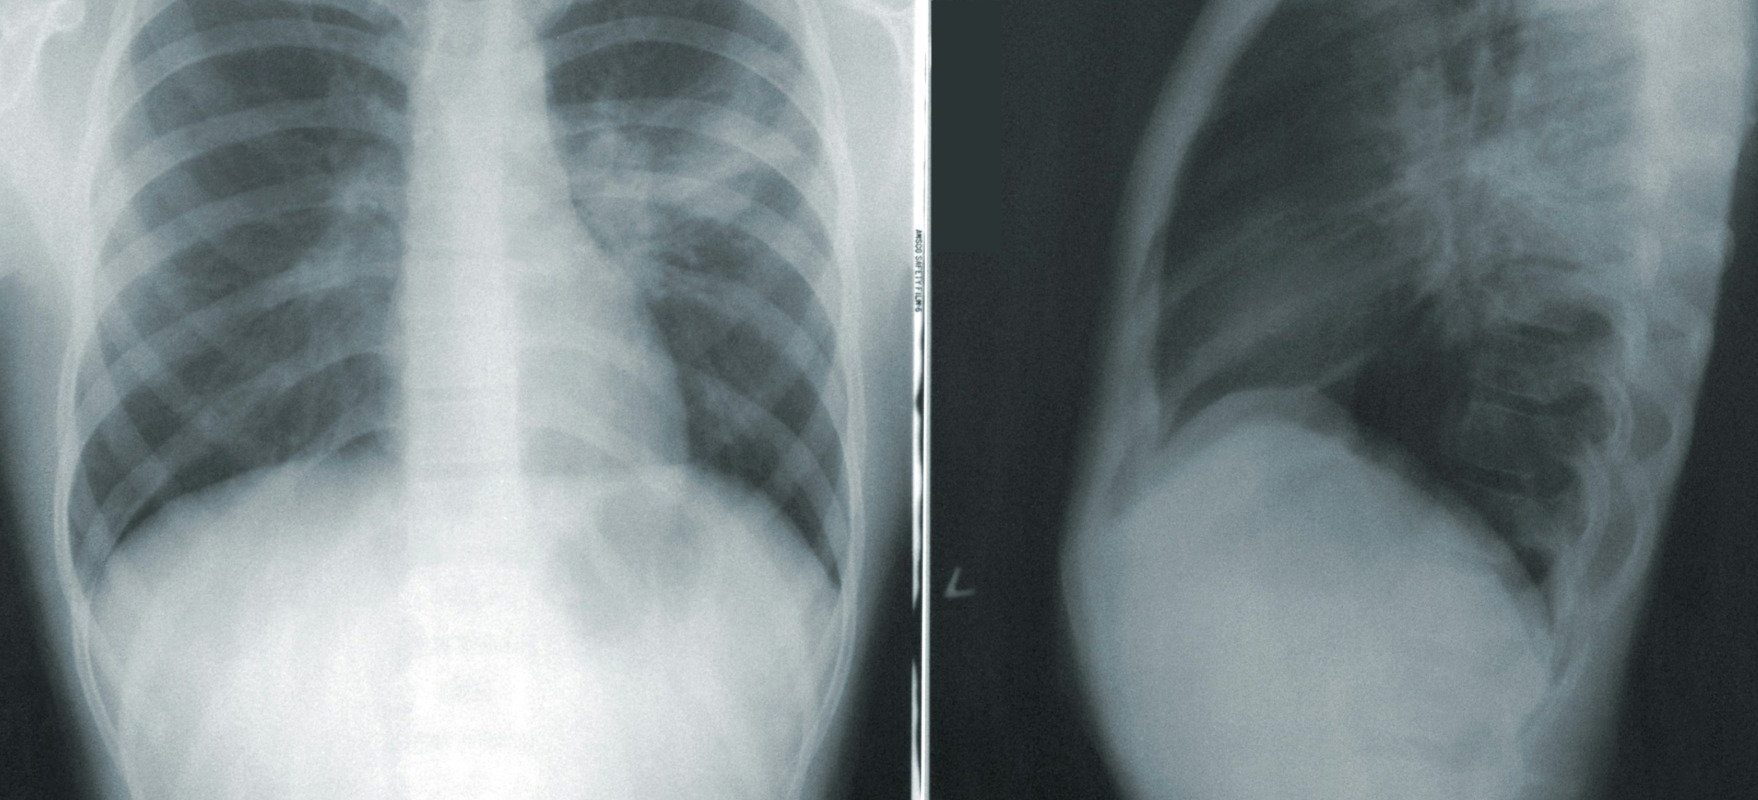

Tuberculoza este o boală tratabilă și prevenibilă, cauzată de o bacterie care afectează cel mai adesea plămânii. Se transmite pe cale aeriană, atunci când persoanele infectate tușesc, strănută sau scuipă.